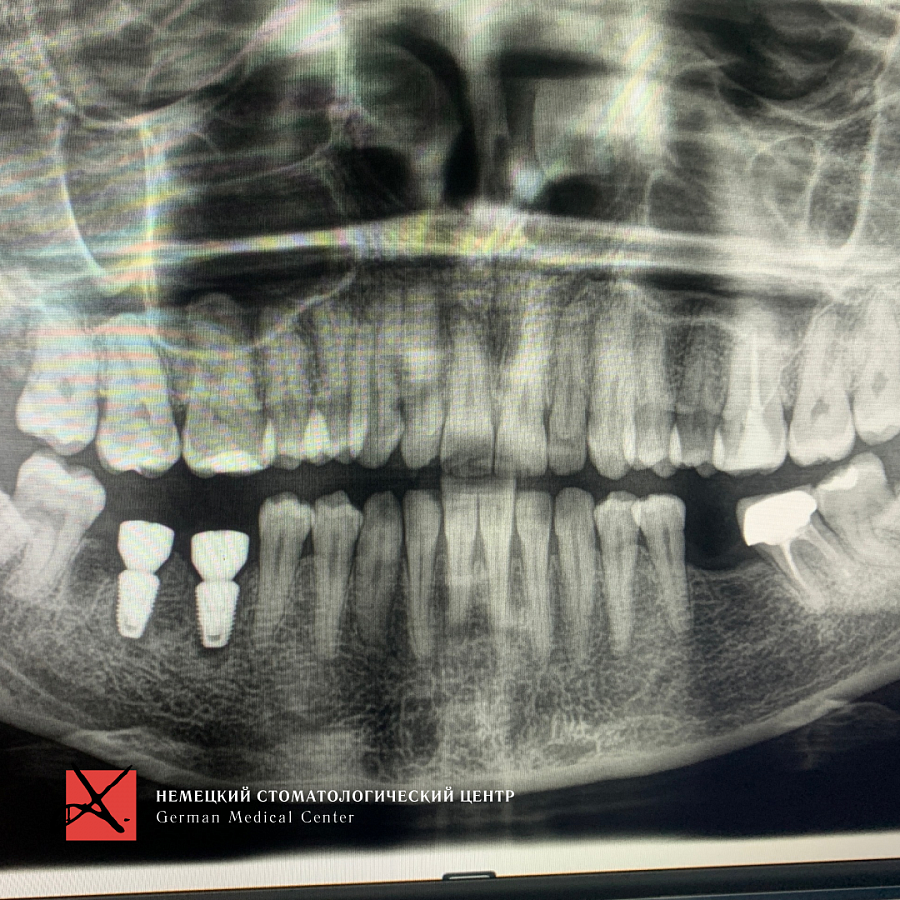

Пациентка обратилась с жалобой на перелом зуба, который ощутила при накусывании.

Провели имплантацию при помощи хирургического шаблона, который позволяет максимально точно спроектировать и спозиционировать положение имплантата для будущей функциональной нагрузки, грамотного распределения давления на имплантаты, а также здоровья зубного импланта. Операция прошла успешно.

Результат лечения